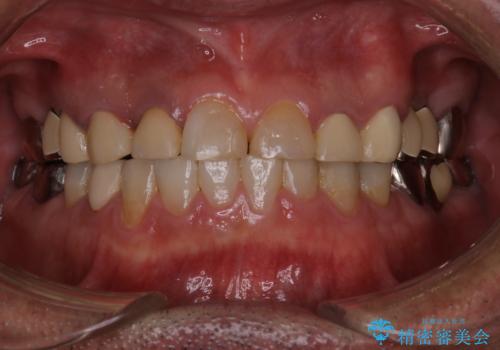

歯肉からの出血 適合の悪い銀歯をオールセラミックのブリッジにやり替え

- 右上奥歯の歯肉から出血があり異和感をおぼえ来院された患者様です。

以前の被せ物を除去し、仮歯に変えてすぐに異和感がとれました。

歯周治療を行い、歯肉が引き締まってから補綴治療しました。